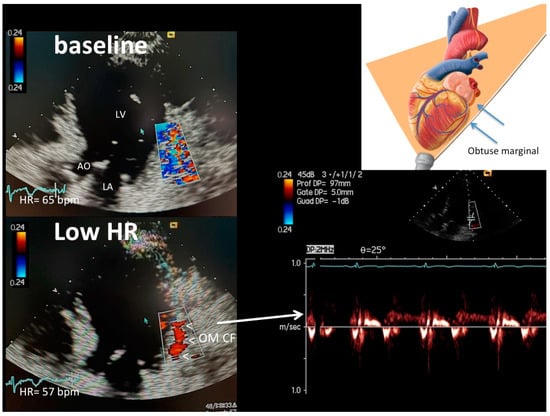

| OM b, 26 seg | 23 (88) | 3 (11) | 0 | 24 (92) | 1 (4) | 1 (4) | 0 |

| OM a, 26 seg | 1 (4) | 12 (46) | 13 (50) * | 1 (4) | 15 (58) | 10 (38) * | 25 (12) ** |